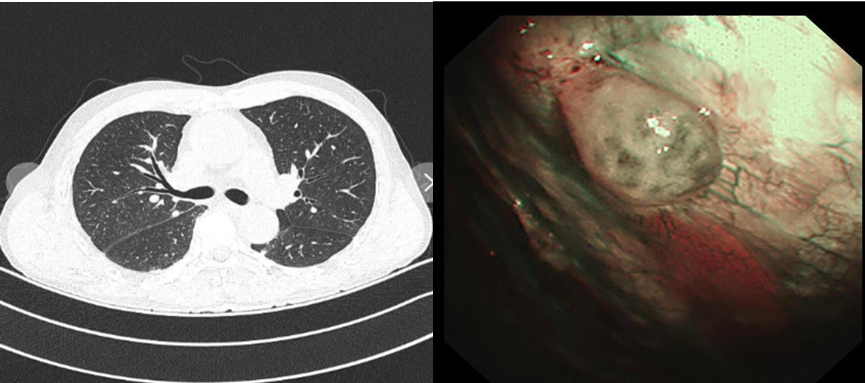

患者刘先生,65岁,因“右侧胸痛一月余”入住我院。此前,刘先生的病情就已几经波折,于外院就诊后,胸部增强CT发现右肺多发结节,较大结节旁囊腔病变。由于刘先生右侧最大结节仅为1.6*1.3cm,病变位置特殊(靠近脊柱旁),常规支气管镜检查和肺穿刺活检均难以精准到位,无法获取准确的病理组织从而难以明确诊断。同时,考虑到如果胸膜内存在转移,手术切除也并非可行之策,明确病理诊断成为医疗团队面前的一道棘手难题,也是能否制定后续精准治疗方案的关键所在。

手术当日,患者左侧卧位,采用局麻方式,经超声精准定位后,于右侧腋中线5-6肋间进行人工气胸操作,内科胸腔镜直视下,可观察到壁层胸膜和脏层胸膜,实时活检。既明确诊断,又确认了分期,术后患者恢复良好。

内科胸腔镜技术”作为呼吸科的重要诊疗手段,主要用于不明原因的胸腔积液的病因检查。相较于传统检查方法,能获取更准确、更足量的组织标本进行病理分析,大大提高疾病诊断的准确率。例如,像刘先生这样常规手段难以确诊的病例,依靠胸腔镜技术不仅明确了肺癌诊断及分型,还进一步完善了肺癌的分期。